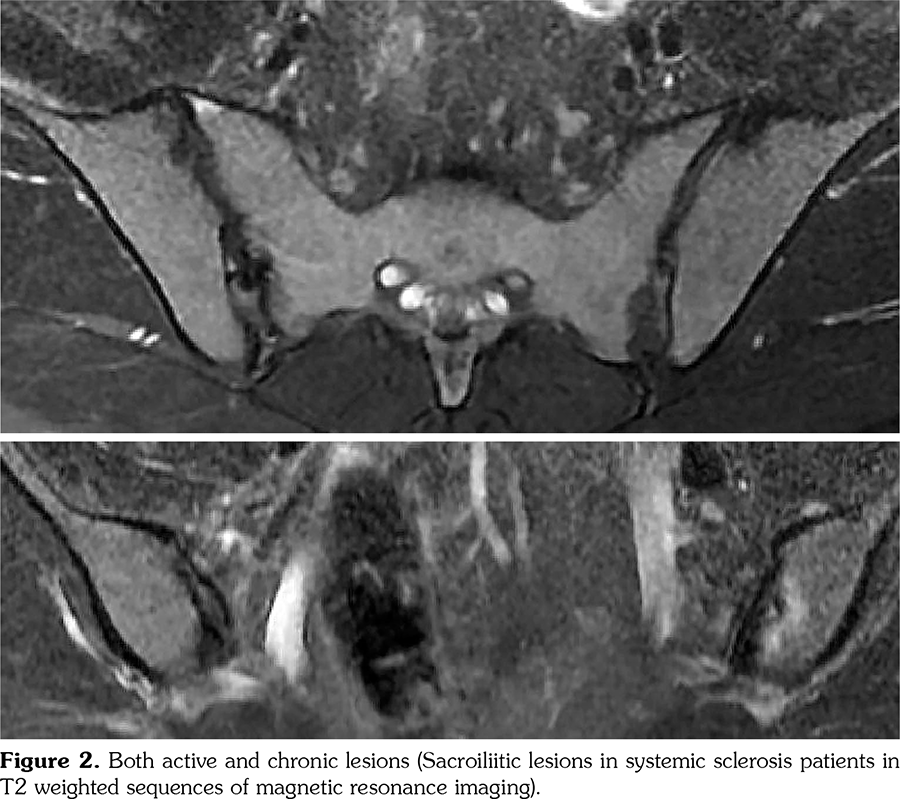

Records of SSc patients admitted to the Department of Internal Medicine, Division of Rheumatology between January 2014 January 2015 were analyzed retrospectively. Of the 157 patients, 30 patients (2 males, 28 females; mean age 44.1±12.5 years; range, 24 to 70 years) who underwent MRI of sacroiliac joints were included in the study. The indications of MRI were musculoskeletal pain or high C-reactive protein (CRP). SSc patients were classified according to the American College of Rheumatology (ACR)/ European League Against Rheumatism (EULAR) 2013 criteria.[8] They were grouped according to the LeRoy criteria as diffuse or limited disease.[9] The clinical data were collected from patient records. T1 and T2 weighted magnetic resonance images of sacroiliac joints were evaluated according to the Assessment of SpondyloArthritis International Society (ASAS)/ Outcome Measures in Rheumatology MRI group criteria (Figures 1 and 2).[10] The ASAS scoring method was applied to conventional radiograms. Presence of inflammatory back pain was assessed as defined by ASAS.[11] Human leukocyte antigen B27 (HLA-B27) test results (if present) and CRP (mg/L) levels were extracted from patient records. The study protocol was approved by the Çukurova University, Faculty of Medicine, Balcalı Hospital Ethics Committee. A written informed consent was obtained from each patient. The study was conducted in accordance with the principles of the Declaration of Helsinki.

Clinical features of the patients are shown in Table 1. Thirty patients (43%) were taking low-dose steroids (<7.5 mg/day prednisolone), while none of the patients was taking high-dose steroids. Twenty-two patients (73%) were on hydroxychloroquine, 12 patients (40%) colchicine, 17 patients (56%) calcium channel blockers, 11 patients (36%) angiotensin converting enzyme inhibitor/angiotensin-receptor blocker, six patients (50%) methotrexate, four patients (13%) cyclophosphamide, three patients (10%) mycophenolate mofetil, and five patients (16%) azathioprine. The time period between CRP test and MRI was 11.9±5.7 days. Sacroiliitis was detected by MRI in 11 SSc patients (37%). Five patients had chronic sacroiliitis, three had active sacroiliitis, and three had both active and chronic forms. For further evaluation, patients were divided into four groups as group 1 (consisting of all patients n=30), group 2 (non-sacroiliitis group, n=19), group 3 (active sacroiliitis group, n=6, three patients with active and three patients with both active and chronic lesions), and group 4 (chronic sacroiliitis group, n=5, patients with only chronic lesions). Radiographic findings, inflammatory back pain, HLA-B27, and CRP results are shown in Table 2. The clinical features of SSc patients with sacroiliitis on MRI are listed in Table 3. Six patients had diagnostic sacroiliitis on conventional radiograms (20%). Five patients (17%), whose conventional radiograms were non-diagnostic, had sacroiliitis detected on MRI. The number of patients with inflammatory back pain in group 3 was five in six patients (83%), whereas it was one in 19 patients in group 2 (5%) (p<0.05). CRP levels were significantly higher in group 3 compared to group 2 (p<0.05). No other clinical or laboratory parameters were found to be statistically significant between the study groups. When considering all data, seven patients were eligible for being classified as SpA according to ASAS criteria as shown in Table 2. No additional clinical features related to SpA were reported in these seven patients such as uveitis, psoriasis or inflammatory bowel disease.